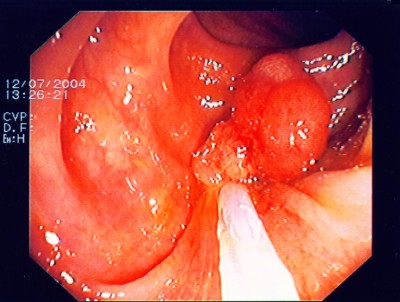

Großer Polyp des Dickdarmes